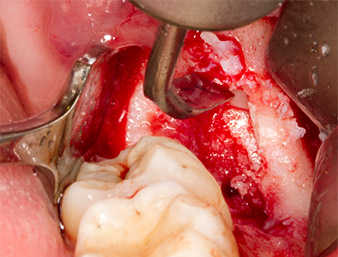

To obtain autogenous material for subsequent wound treatment, healthy bone chips were harvested from the surroundings of the root remnant with a piezo surgical instrument (Piezomed B5) (Fig. 5).

Piezomed B5

Fig. 5: Bone in the region of the alveole is lifted with a chisel-shaped piezo surgical instrument (Piezomed B5). This bone is used as autologous augmentation material after removal of the root remnant (cf. Fig. 13 and 14).

The autogenous tissue was removed with the scraper-shaped section of the working part of the instrument and stored in a physiological saline solution until further use (cf. Fig. 13).

To expose the root remnant with as little trauma as possible to the tissue, a further instrument was used (Piezomed S2) that is primarily indicated for preparing the lateral window in augmentations of the sinus floor. The diamond-coated ball was additionally used to smooth sharp bone edges (Fig. 6 and 7). All the Piezomed attachments were used with the relevant automatic default setting without booster function.

Piezomed S2

Fig. 6: The root remnant is carefully exposed with a diamond-coated spherical instrument (Piezomed S2), bone edges are smoothed.

root remnant 38

Fig. 7: The root remnant 38 (LL8) is well exposed in its alveole for subsequent removal.